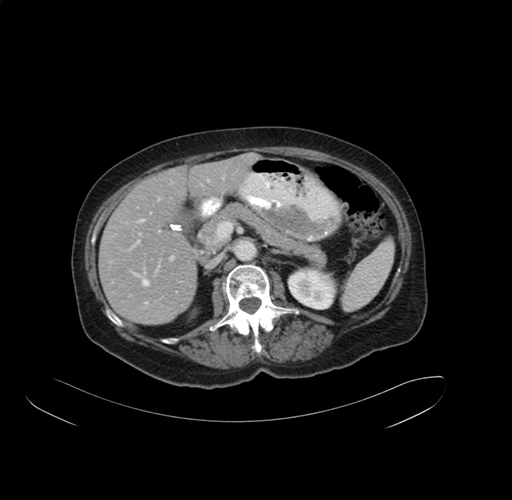

Pre-Chemo: Axial Venous

Axial Venous